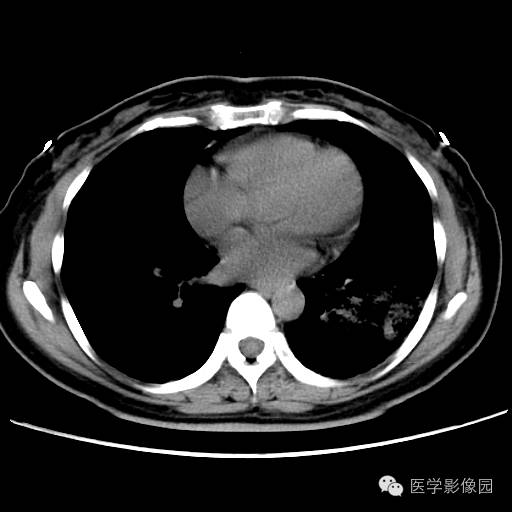

肺叶实变性支气管肺泡癌1例CT影像表现